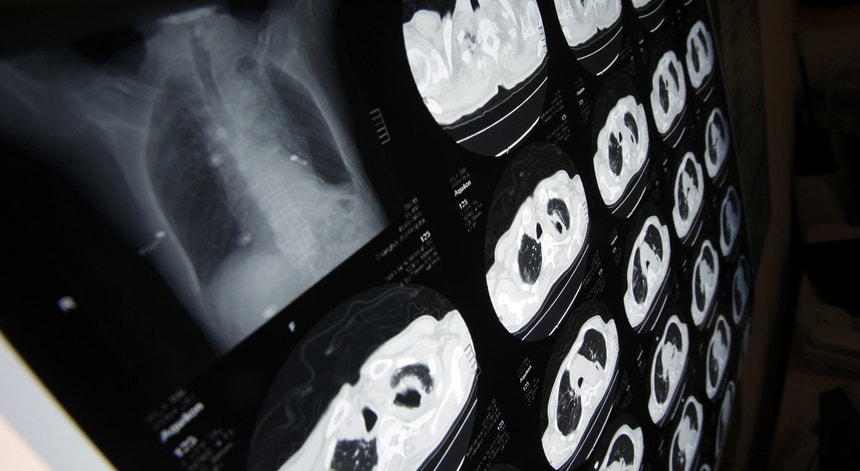

Doenças do aparelho circulatório e tumores malignos foram os responsáveis por mais de metade das 110.970 mortes registadas em Portugal em 2016, divulgou hoje o Instituto Nacional de Estatística (INE).

Em "Causas de Morte 2016", os números do INE traduzem um aumento de 2,7 por cento nas mortes por tumor maligno em relação a 2015, subindo para 27.357, com uma idade média de 73,1 anos e custando 111.072 potenciais anos de vida perdidos para as doenças.

Os tumores malignos da traqueia/brônquios/pulmão e os do cólon, reto e ânus foram os mais mortíferos, tirando a vida a mais de 8.000 pessoas.